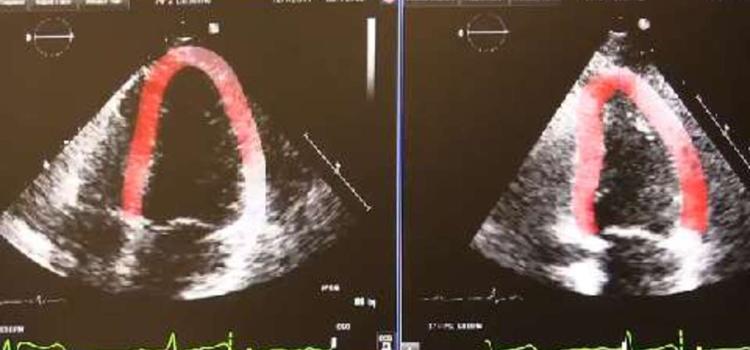

This channel includes news and new technology innovations about cardio oncology, the subspeciality of monitoring, preventing and treating cardiovascular damage caused by cancer treatments such as chemotherapy and radiation therapy. Chemo and radiation can damage or kill cardiac muscle cells, which can result in reduced cardiac pumping capacity. The speciality of cardio-oncology monitors cardiac performance with a baseline echocardiogram and followup imaging during treatments to ensure the heart is not damaged.

June 19, 2018 — Clinical practice, along with guidelines and research, have shown that speckle tracking strain imaging ...

May 3, 2017 — Epsilon Imaging Inc. announced a research study using EchoInsight was presented at the American College of ...

June 17, 2016 — Epsilon Imaging Inc. announced a research study was presented at the American Society of ...